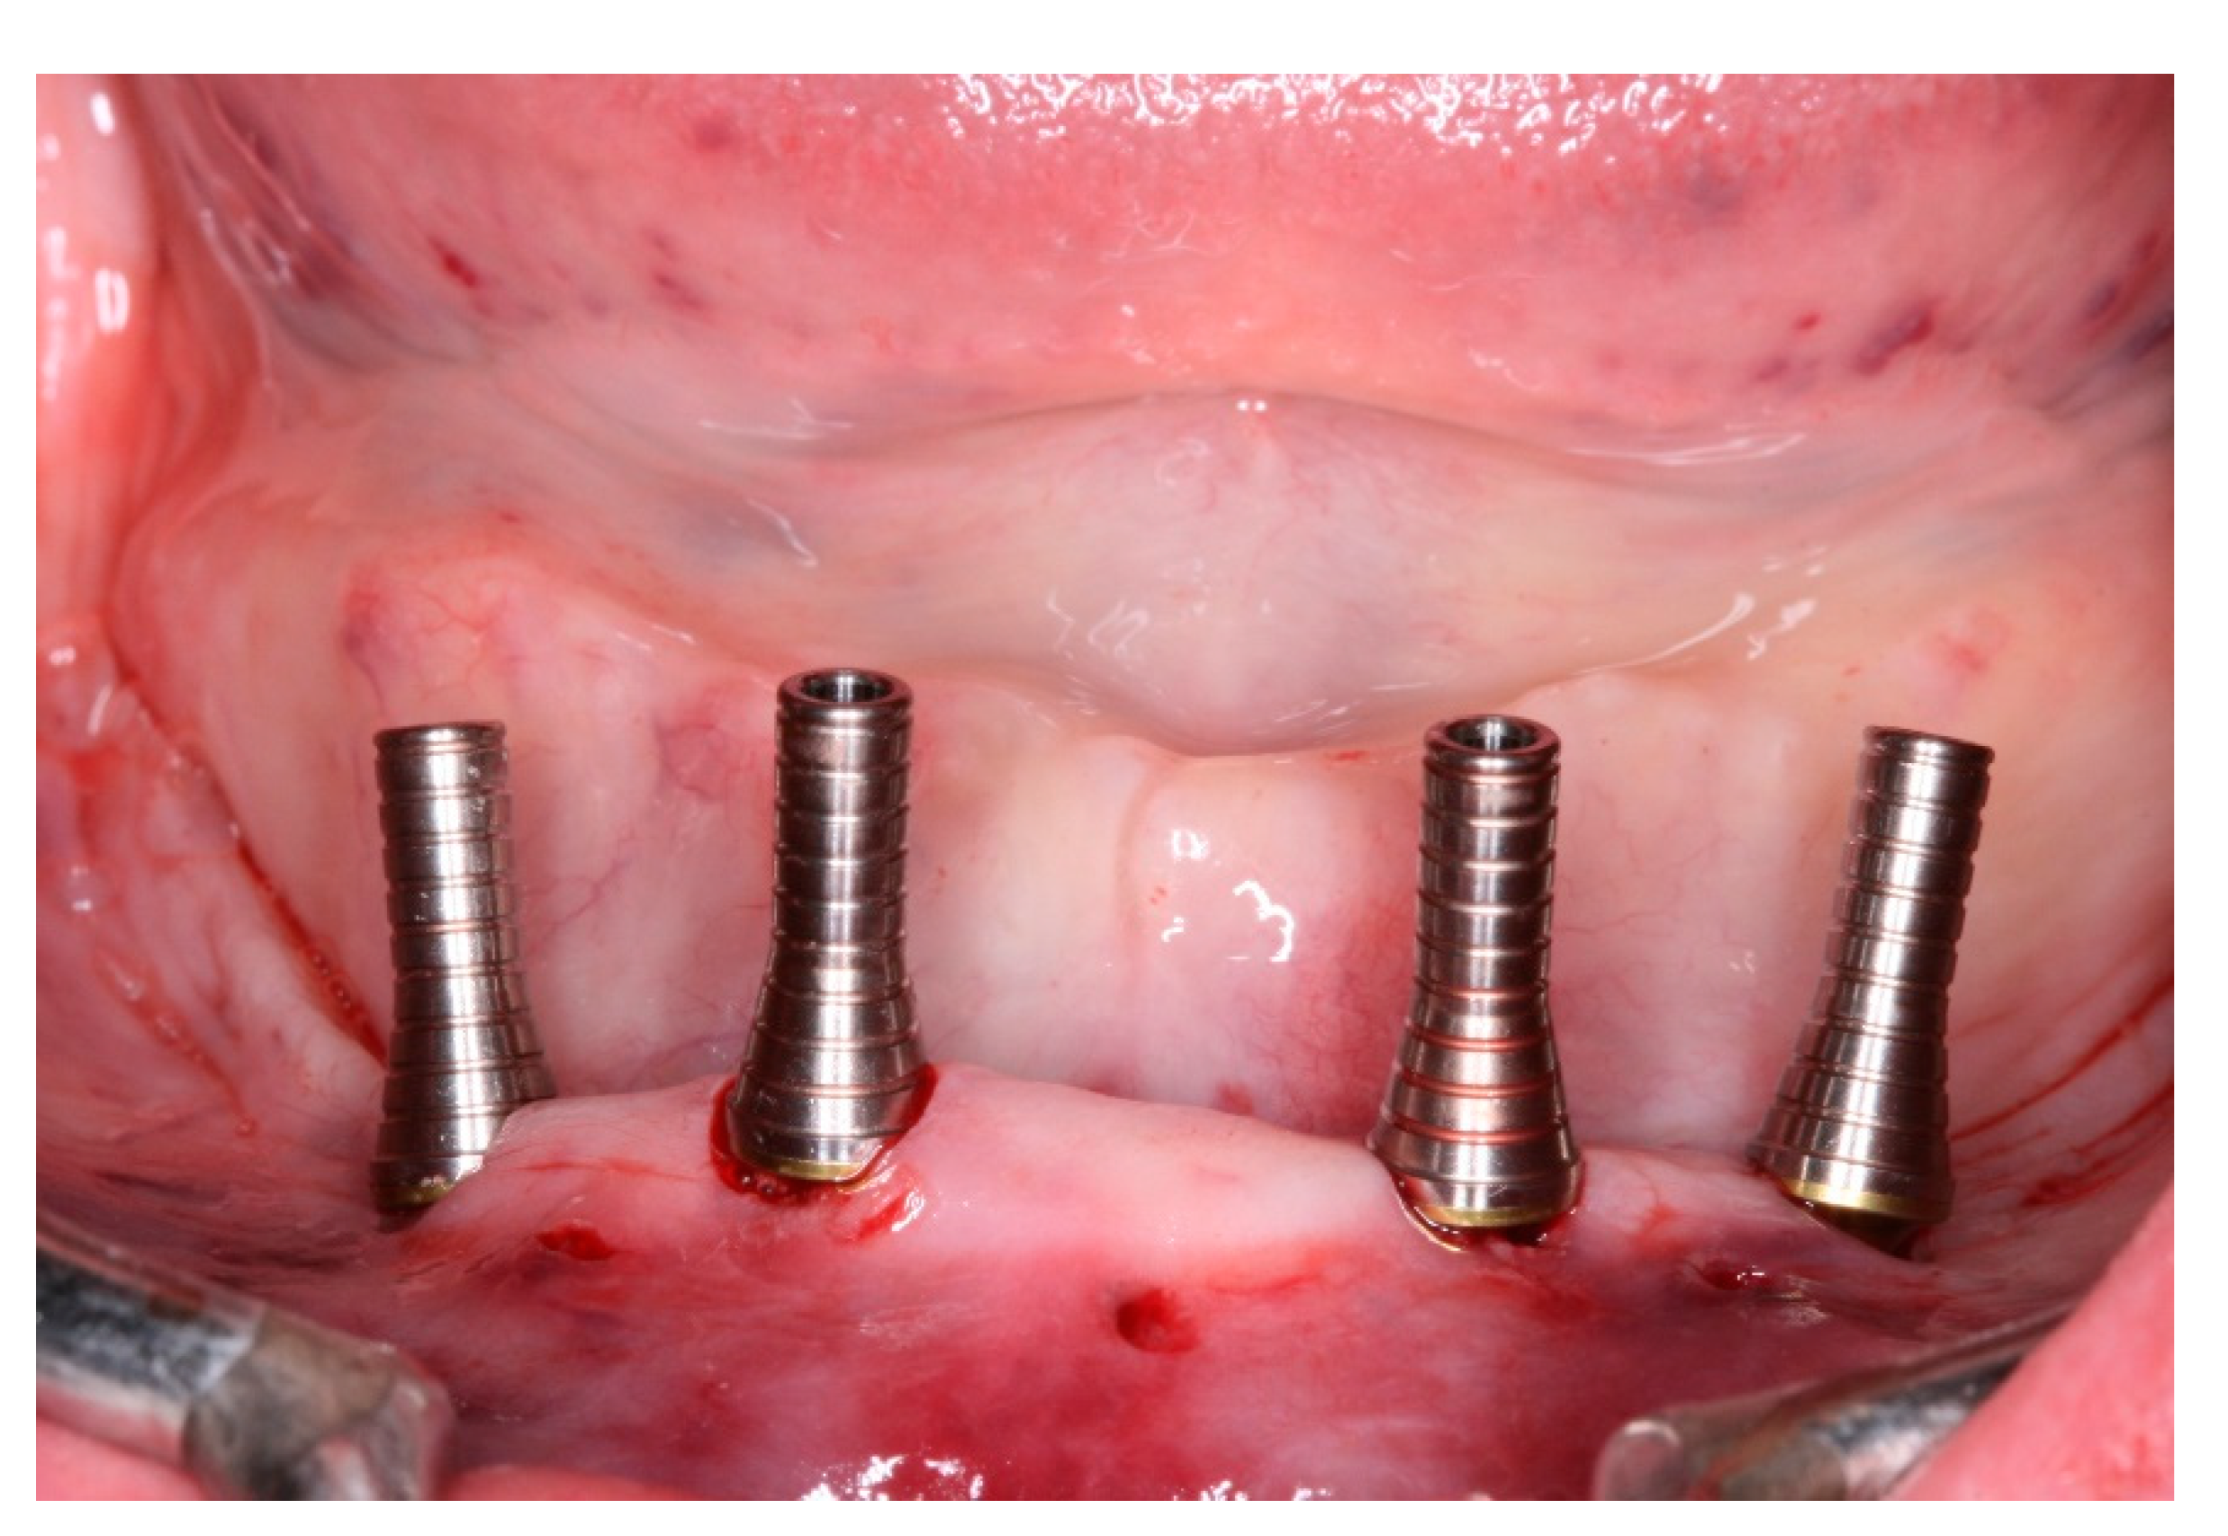

Pre-operatory medication consisted only on 2g of Amoxicillin one hour before the procedure, as suggested by her cardiologist. On surgery day, after anesthesia with Articaine 4% 1: 100,000 (DFL, Rio de Janeiro, Brazil), the computed surgical guide was placed in position, assured by the oclusal position on both sides and the stability over the patient’s mucosa, and in this position, fixed with the fixation pins after using their drills, assuring the guide immobilization (Figure 7). After that, we followed the guided bone instrumentation protocol recommended by the Plenum implant system (Plenum® Bioengenharia- Jundiaí, Brazil) to place 4 dental implants of 4.0x10mm with morse-tapper connection, produced by addtive manufacturing technology using titanium powder grade 23 (Figure 8), without raising a flap (Figure 9 and Figure 10). Because of this detail, very little bleeding was noted during the surgery. All implants were inserted with insertion torque ranging from 45 to 60 N/cm, assuring us the possibility for immediate load. The guide was removed (Figure 11) and four mini-conic abutments (Plenum® Bioengenharia- Jundiaí, Brazil), with 2mm high were installed on the implants. No suture was necessary and minimum trauma was noted on the soft tissue (Figure 12). Over these abutments, titanium cylinders were installed (Figure 13) and the lower denture was prepared to capture the implants position, translating the removable prosthesis into a fixed one (Figure 14 and Figure 15). Pattern Resin was used to unite the denture to the cylinders, and over the red resin, pink acrylic resin was used to improve the aesthetic appearance of the prosthesis. The denture was worn out in order not to touch the patient’s mucosa, and to diminish the cantilever we removed the molars from both sides of the denture (Figure 16) and installed the temporary fixed screw retained full-arch rehabilitation (Figure 17 and Figure 18). With this, the patient left the surgical appointment with an immediate load implant rehabilitation. Post operatory medication consisted on 600mg of Ibuprofen, twice a day during 3 days, if necessary. She was instructed to put ice bags on the surgical area during 48 hours, about 15 minutes every hour. On the day before surgery the patient suspended the medication because she had no pain. The patient was also instructed not to sleep with the opposing complete denture for 7 days and feed only with soft foods.

Figure 11. View of the mucosa immediately after surgical guide removal and implants placement.